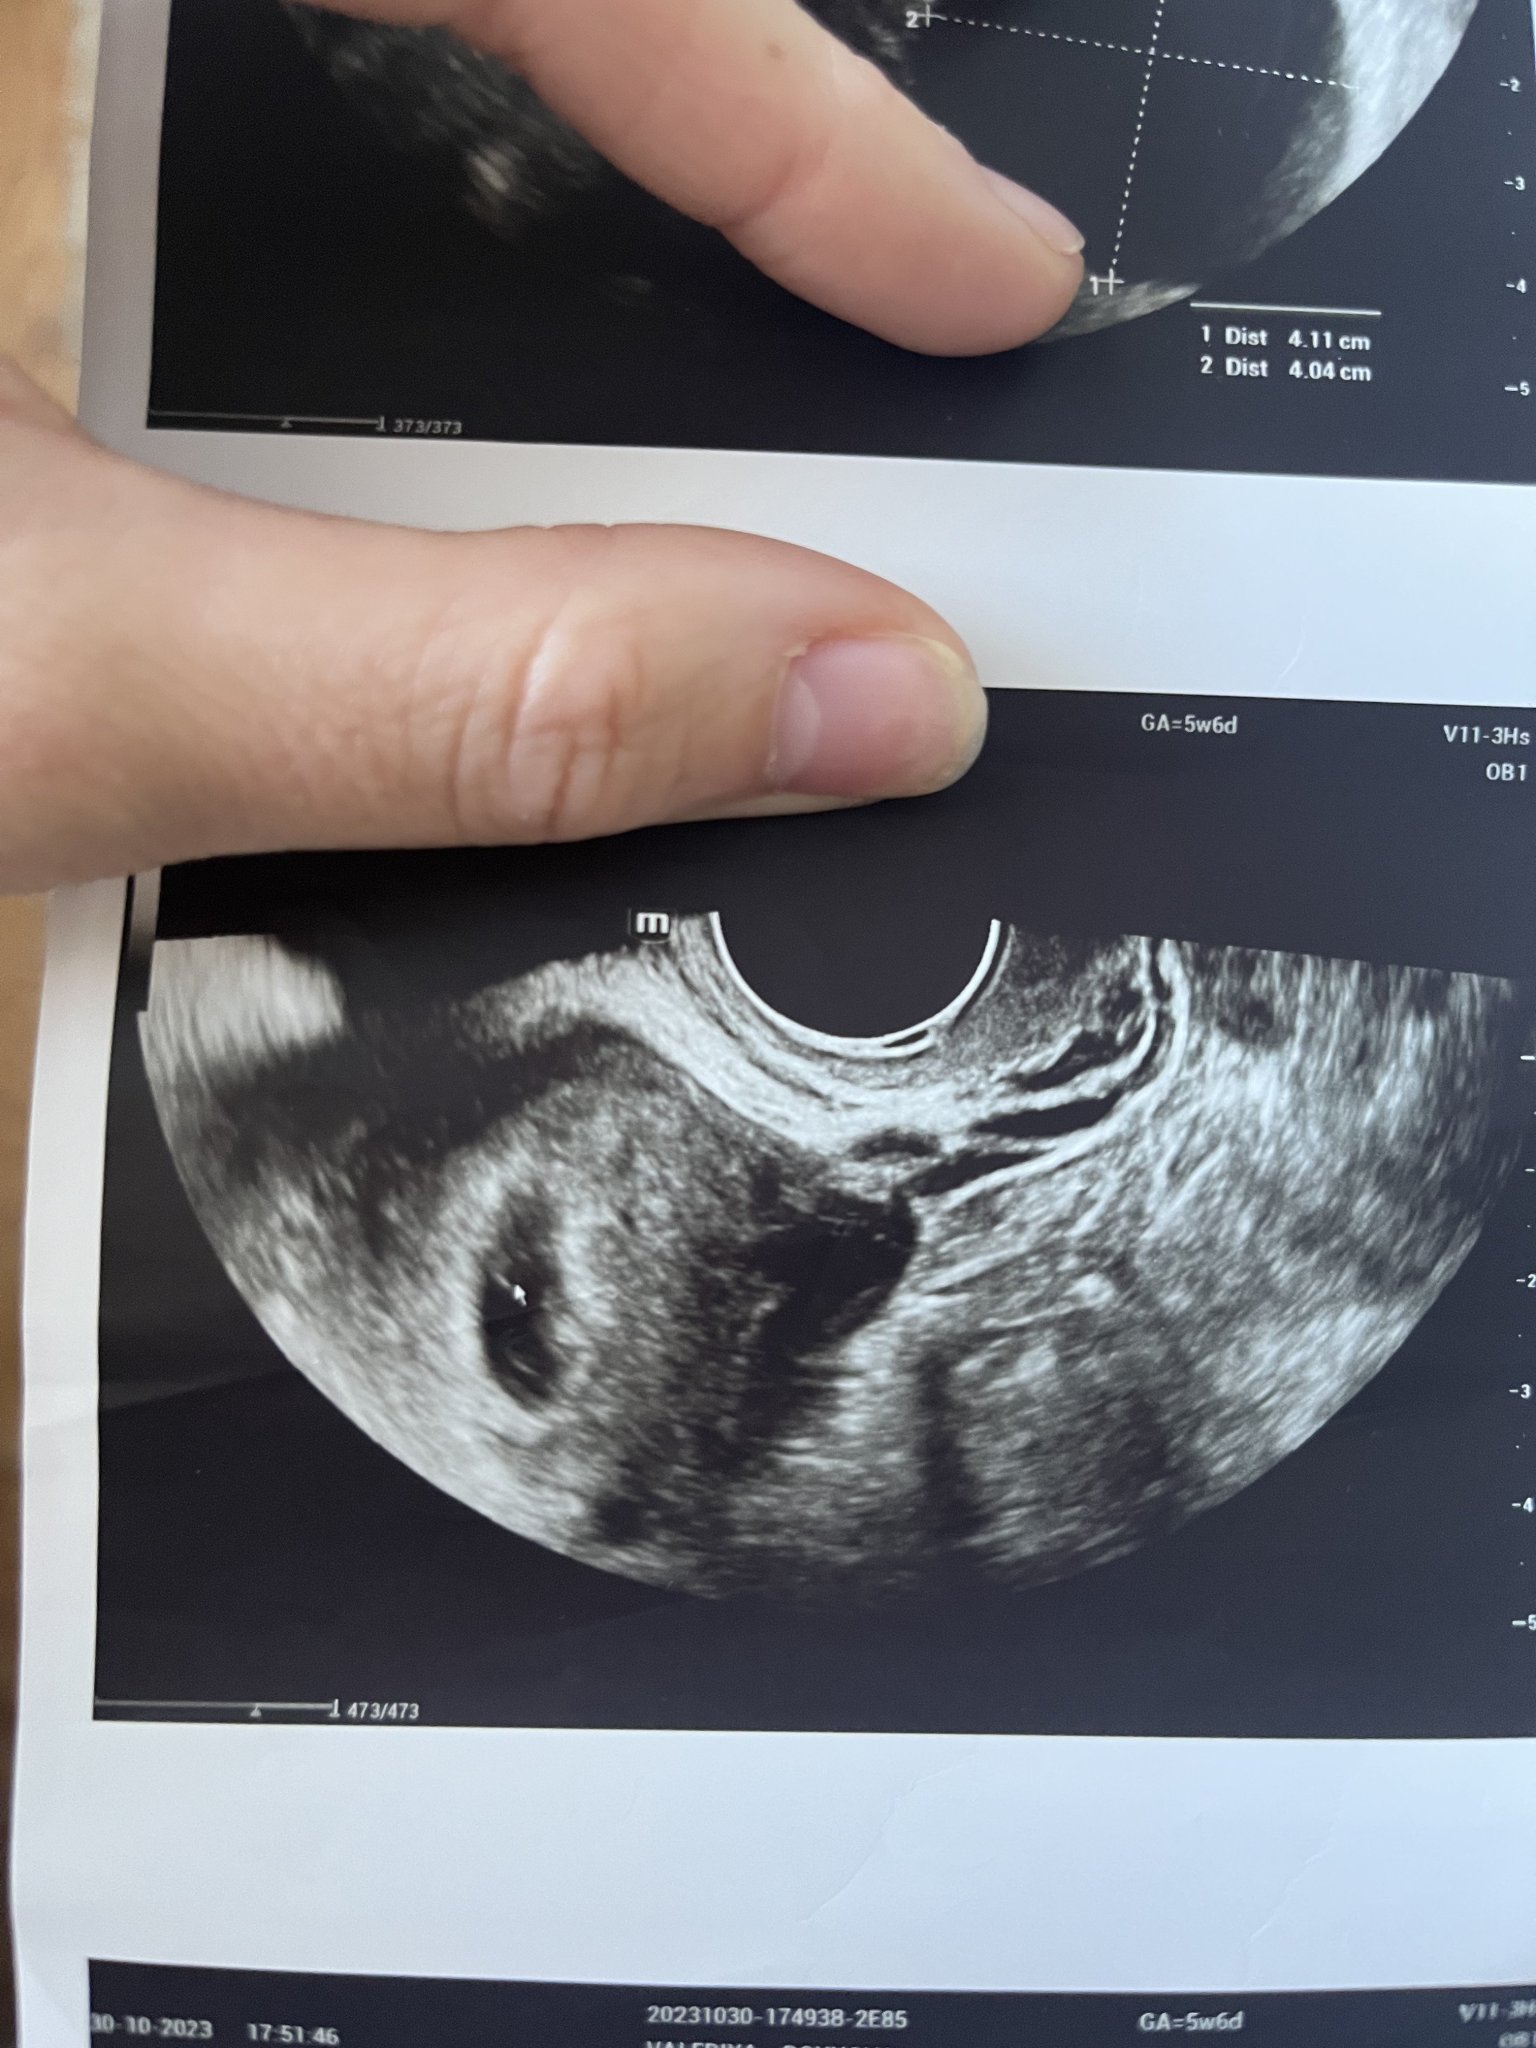

Първия ден на последната ми менструвация беше на 19.09.2023г. 4 положителни теста за бременност. Вччера беше първият ми преглед. Прикачам снимките от него. Видя се плоден сак с размер 18мм, ембрион не. Аз съм с две матки и плодния сак е в лявата матка. В левия яйчник имам и 40мм киста Sad . Притеснено ми е защо при тази големина на плодния сак не се видя ембрион. Преди 8 месеца претърпях куха беменност и се притеснявам изключително много да не се повтори. Чак след месец ще ми бъде следващия преглед, а до тогава ще се побъркам. Моля, ако някой може да помогне със съвет или е бил в подобна ситуация, да пише. Благодаря! Simple Smile

На мен ми изглежда че има нещо в сакчето, не е празно. Ако ще ви успокои, пуснете си чхг  през 48 часа да видите дали се удвоява или отидете още някъде на преглед, да не чакате още месец. Успех!